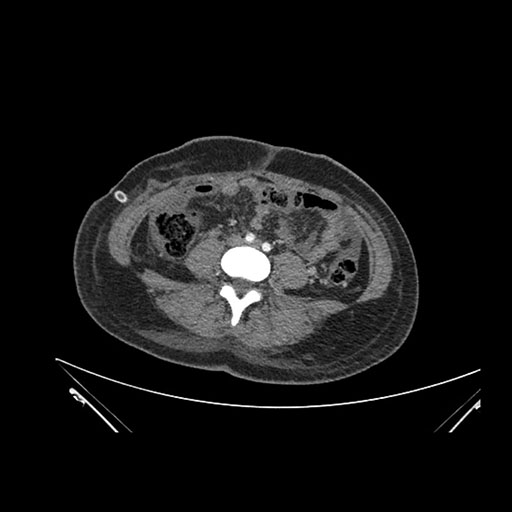

Imaging Analysis

Look through the patient's CT scan to identify any areas of concern for the necessary procedure.

Axial Venous

Based on initial findings, which issue(s) would you be most concerned about?